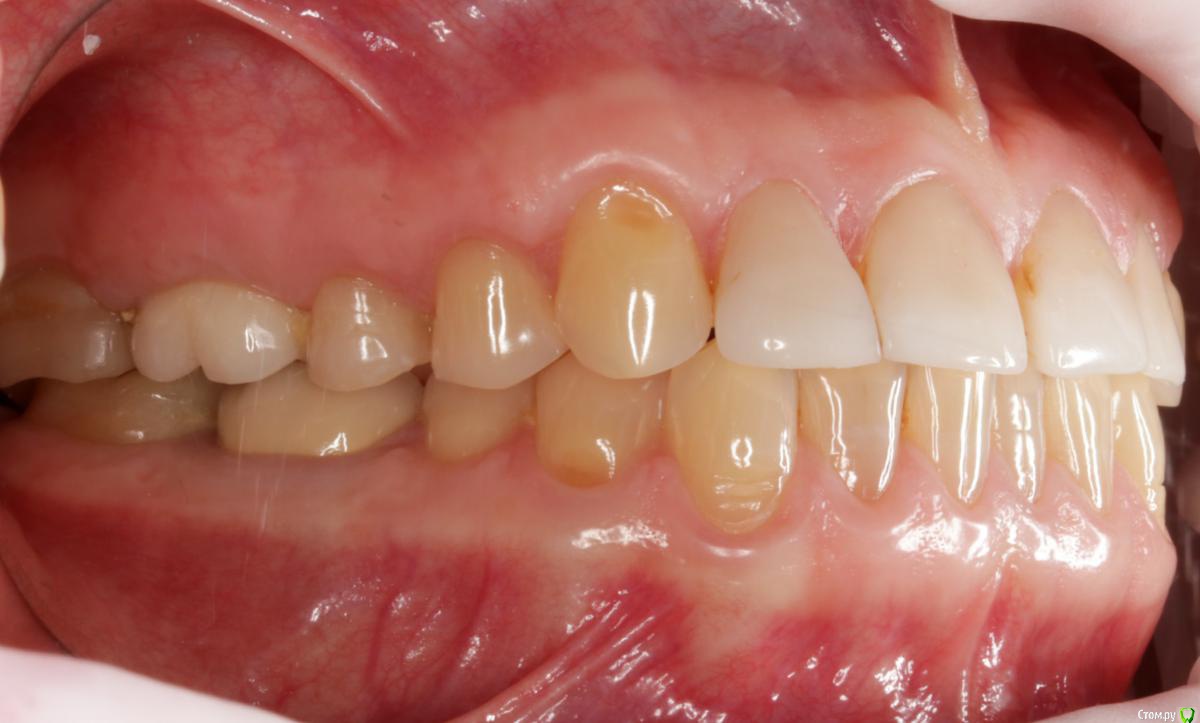

Dmitry DK Опубликовано 10 сентября, 2019 Поделиться Опубликовано 10 сентября, 2019 Фотопротокол к сожалению не полный, но ничего особенного и не проводилось. 1) Открытый синус, удален пломбировочный материал из пазухи, уложен 1 г Bio-oss 2) через 6 мес имплантация Straumann SP 4.1\10 Результат через год 9 Ссылка на комментарий

Irouil Опубликовано 10 сентября, 2019 Поделиться Опубликовано 10 сентября, 2019 Классный результат, только я бы не разделял хирургические этапы 1 Ссылка на комментарий